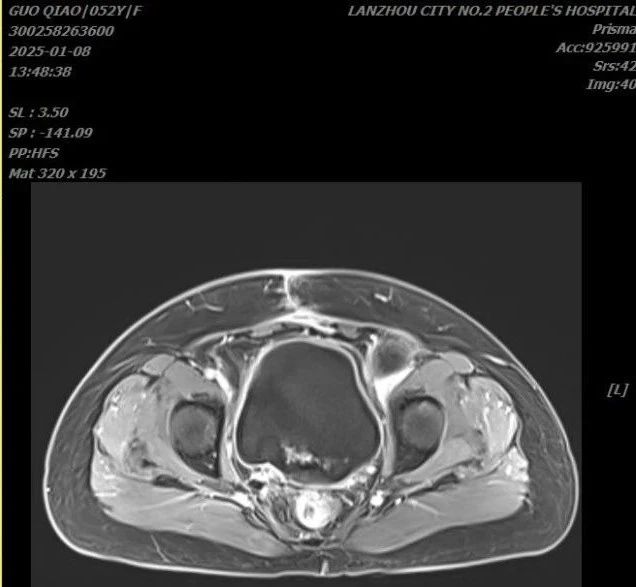

腹盆腔MRI宫颈癌术后化疗,左侧髂窝囊性灶,盆腔少量渗出,盆壁间隙少量渗出,双侧髂窝多发淋巴结,较大者位于右侧,请结合临床并复查。

治疗前

治疗后

放疗过程顺利,复查提示病情稳定